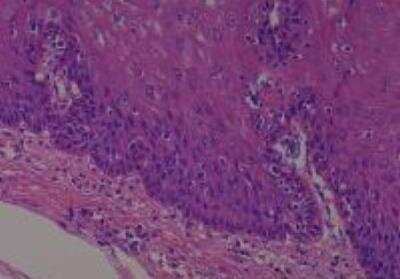

Scientific Data Images for Human Multi Tissue MicroArray (Normal Adjacent)